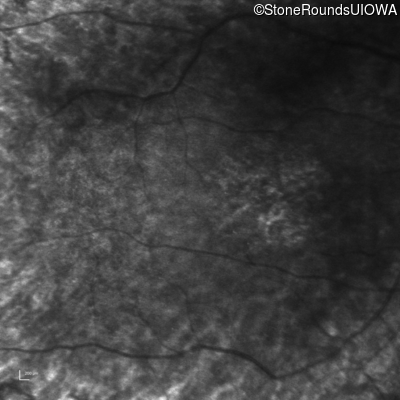

Infrared Fundus Photograph - Right - Hand Motion 1' sc

Exemplar